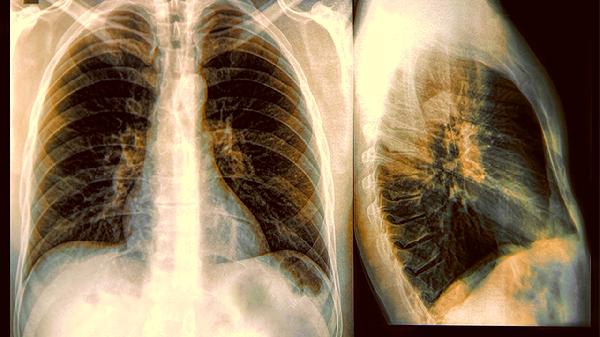

2、影像学检查要精准

X光片看骨骼,B超查肝胆,低剂量螺旋CT筛查肺部,不同部位要选对检查方式。